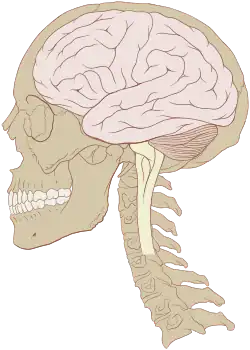

Neuro-oncology is the study of brain and spinal cord neoplasms, many of which are (at least eventually) very dangerous and life-threatening (astrocytoma, glioma, glioblastoma multiforme, ependymoma, pontine glioma, and brain stem tumors are among the many examples of these). Among the malignant brain cancers, gliomas of the brainstem and pons, glioblastoma multiforme, and high-grade (highly anaplastic) astrocytoma/oligodendroglioma are among the worst.[1] In these cases, untreated survival usually amounts to only a few months, and survival with current radiation and chemotherapy treatments may extend that time from around a year to a year and a half, possibly two or more, depending on the patient's condition, immune function, treatments used, and the specific type of malignant brain neoplasm. Surgery may in some cases be curative, but, as a general rule, malignant brain cancers tend to regenerate and emerge from remission easily, especially highly malignant cases. In such cases, the goal is to excise as much of the mass (tumor cells) and as much of the tumor margin as possible without endangering vital functions or other important cognitive abilities. The Journal of Neuro-Oncology is the longest continuously published journal in the field and serves as a leading reference to those practicing in the area of neuro-oncology.

Primary brain tumors can occur at any age, from infancy to late in life. These tumors often afflict people during their prime years. Factors such as age, tumor location, and clinical presentation are helpful in differential diagnosis. Most types of primary brain tumors are more common in men with the exception of meningiomas, which are more common in women.[2]

Cancer spreads to the nervous system by direct invasion, compression, or metastasis. Direct invasion or compression from continuous tissues relates to the proximity of the nervous system to other structures, such as the brachial plexus, lumbosacral plexus, vertebral neuroforamina, base of skull, cranium, and pelvic bones.[2]